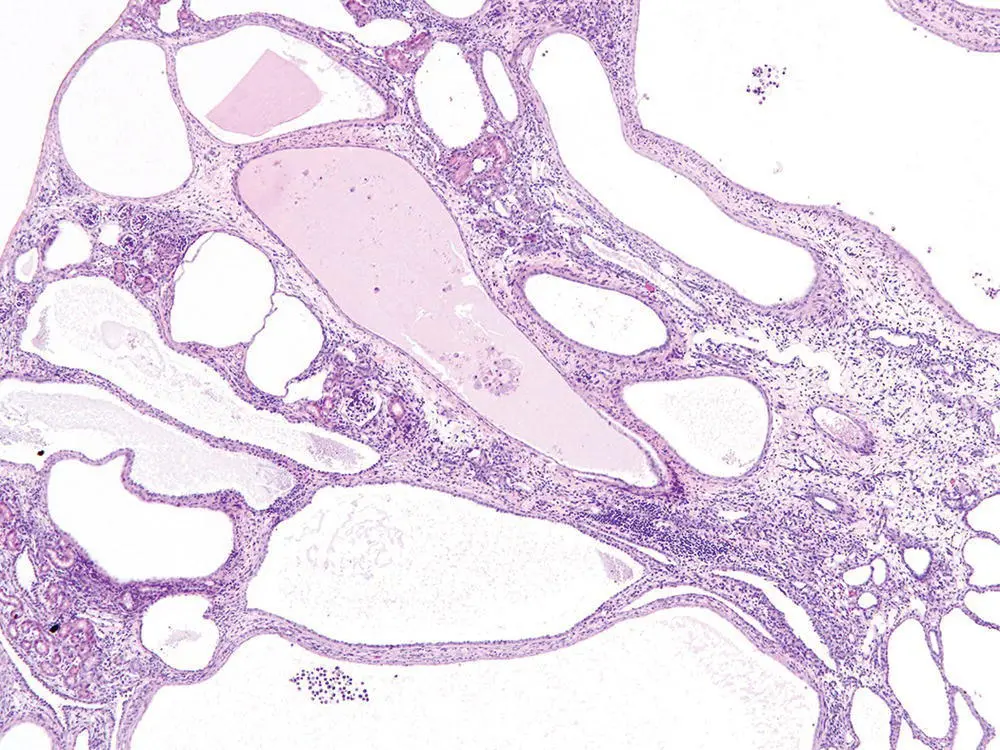

PKDs were the first to be linked definitively to defects in primary immotile cilia. Recognition that polycystin 1 (PKD1), polycystin 2 (PKD2), and nephrocystin 1 (NPHP1) proteins were all localized to the primary cilium/basal body/centrosome provided the first evidence that dysfunctional primary cilia could be involved in the pathogenesis of PKD and nephronophthisis (NPHP) [47, 48]. Since then mutations in dozens of other cilia‐related genes have been directly linked to the development of cystic kidney diseases [49]. The primary cilium on renal tubular epithelial cells projects into the urinary space and appears to act as a mechanosensor in detecting the flow of urine and thereby influencing renal cell division [50]. The primary cilium also regulates the orientation of cell division and disrupted planar cell polarity signaling also contributes to renal cystogenesis [51]. PKD is characterized by grossly enlarged kidneys, due to markedly dilated renal tubules lined by epithelial cells showing increased mitotic activity ( Figure 6.4). In contrast, the polycystic kidneys in NPHP are essentially normal or reduced in size, with low mitotic rates and increased apoptosis of renal tubular epithelium [52] ( Figure 6.5).

Figure 6.5 Nephronophthisis. Cystic tubules with interstitial inflammation and fibrosis in a normal sized kidney are associated with attrition of renal epithelium due to dysfunctional primary cilia.